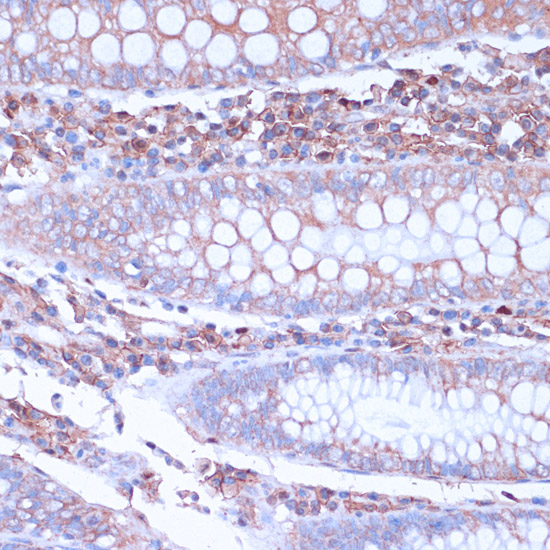

Immunohistochemistry of paraffin-embedded human colon using CD38 at dilution of 1:100 (40x lens).